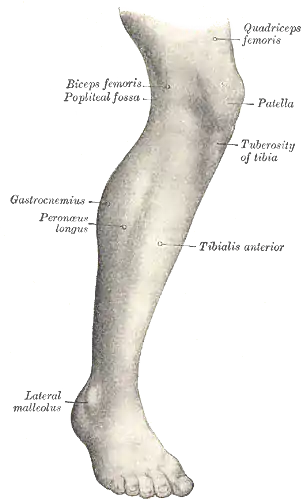

Lateral aspect of right leg | |

The leg is the entire lower limb of the human body, including the foot, thigh or sometimes even the hip or buttock region. The major bones of the leg are the femur (thigh bone), tibia (shin bone), and adjacent fibula. The thigh is between the hip and knee, while the calf (rear) and shin (front) are between the knee and foot.[1]

In human anatomy, the lower leg is the part of the lower limb that lies between the knee and the ankle.[1] Anatomists restrict the term leg to this use, rather than to the entire lower limb.[5] The thigh is between the hip and knee and makes up the rest of the lower limb.[1] The term lower limb or lower extremity is commonly used to describe all of the leg.

The leg from the knee to the ankle is called the crus.[6] The calf is the back portion, and the tibia or shinbone together with the smaller fibula make up the shin, the front of the lower leg.[7]

Surface anatomy of human leg